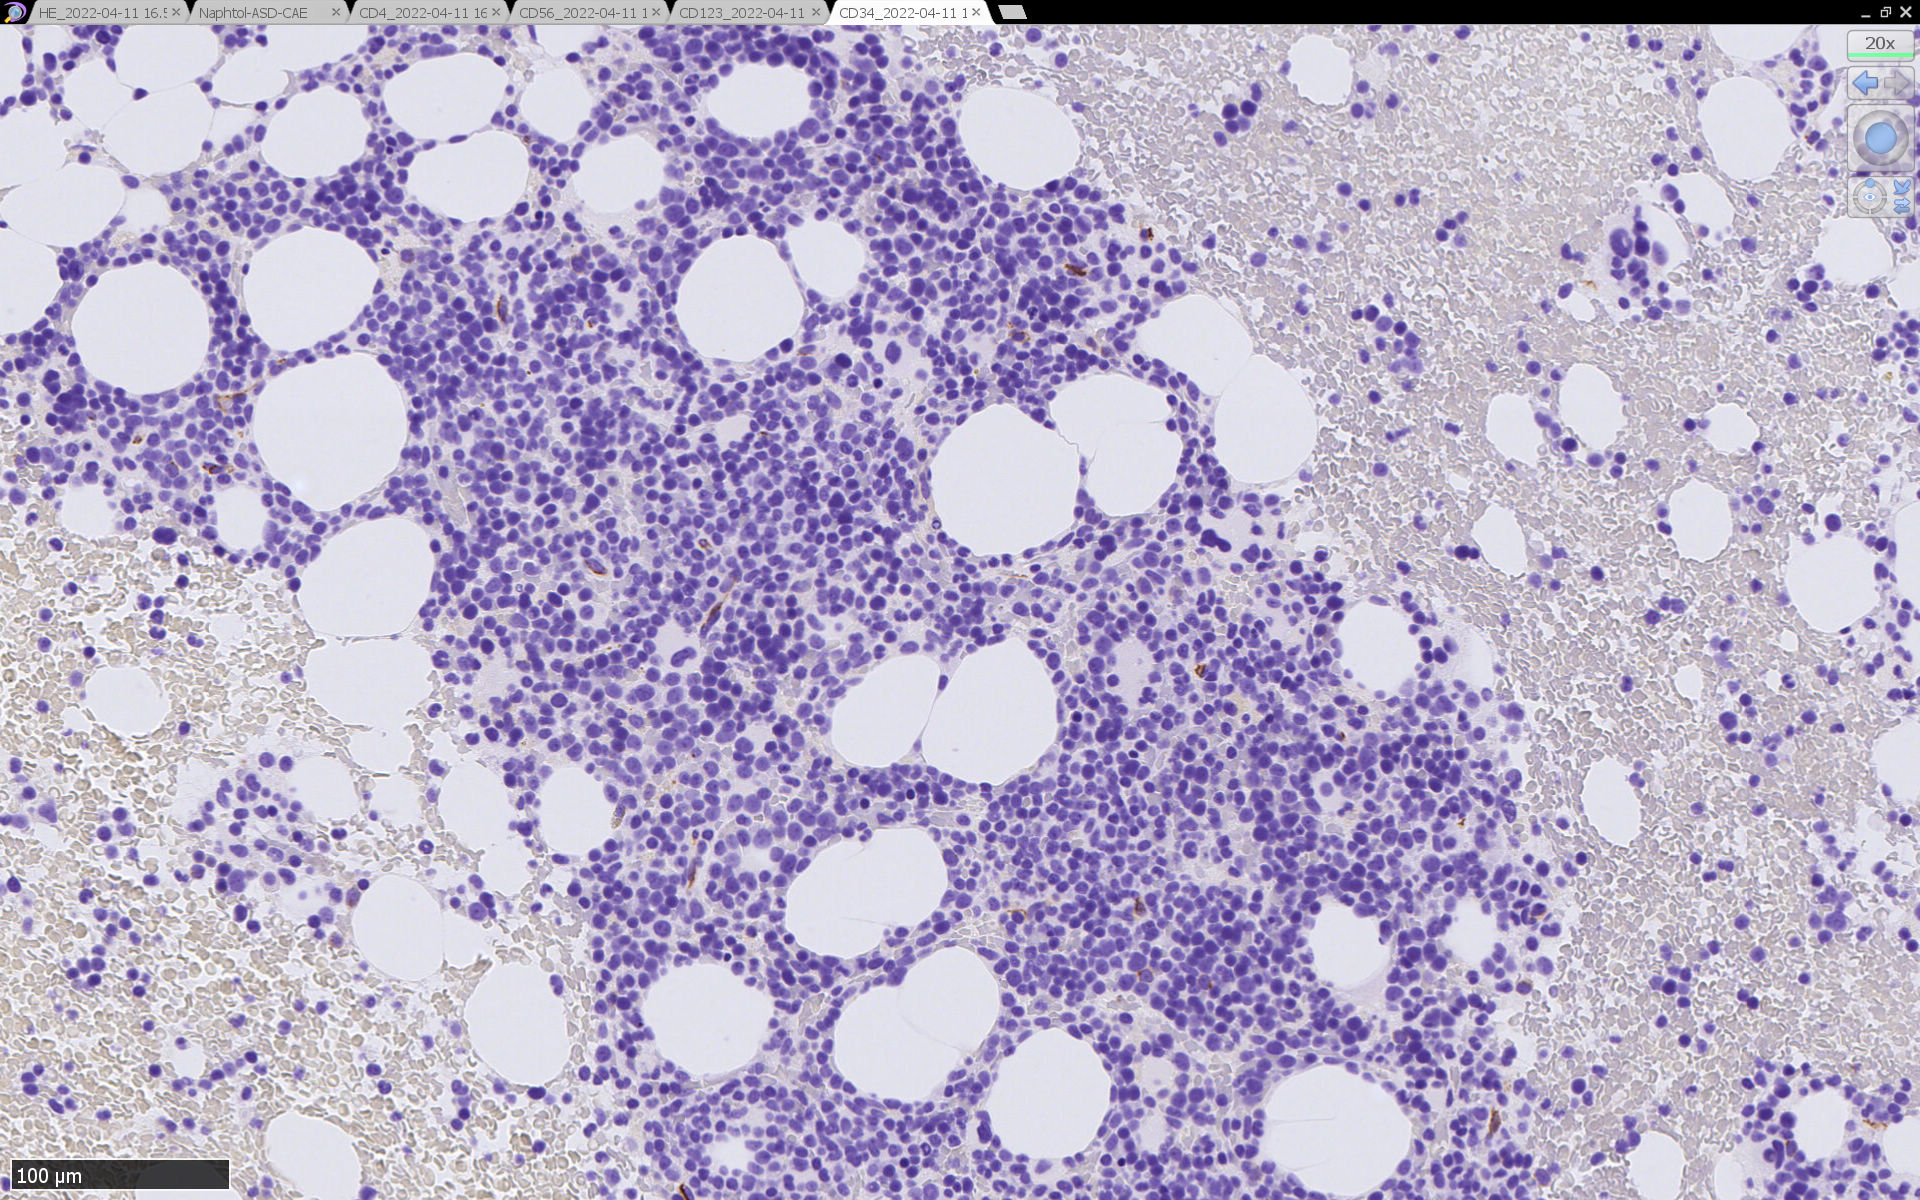

免疫染色

CD4は染まりすぎの感がある(濃く染まる細胞はCD4+ T-cellかもしれない). CD56, CD123が陽性で可能性が高くなり, BPDCNの診断にはCD34は陰性であることが必要

TCF4、CD123、TCL1をconsultationにより染色していただき, 陽性を確認した. CD34-, lysozyme-, CD123(おいてある病院は少ないかも)をしらべて, BPDCN研究会あてconsultationをする流れでしょうか.

免疫染色では, HbFを発現する赤芽球の集簇巣が散見しているほか, p53陽性細胞が軽度に増加している. CD34陽性細胞増加はなし.CD42b染色でmicroMgkはみられなかった. 異形成造血が強く疑われる.